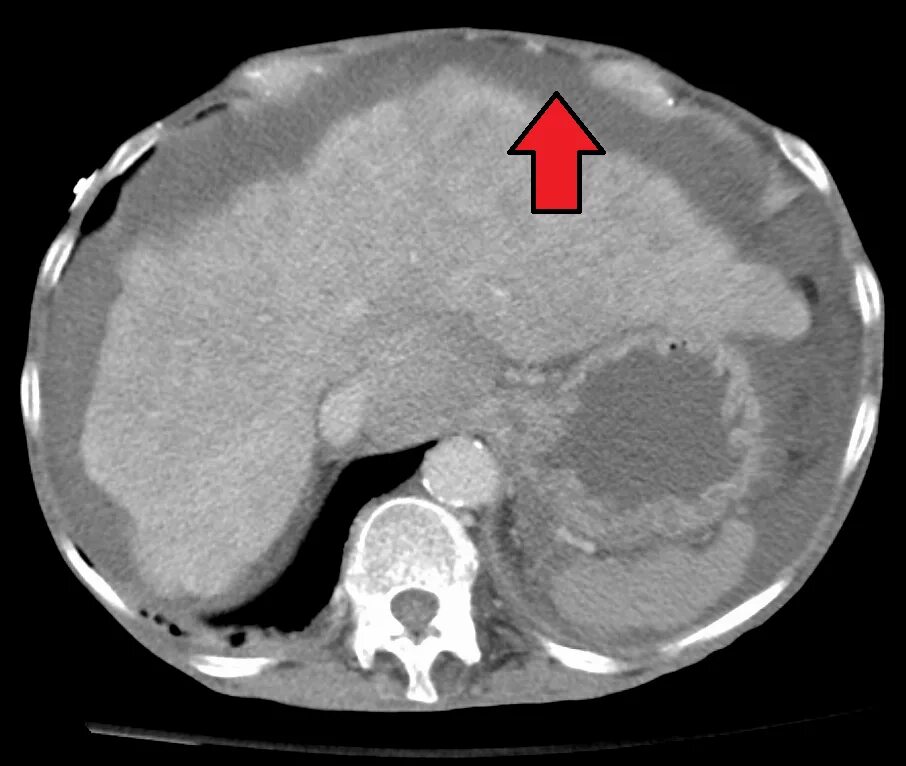

Цирроз печени кт